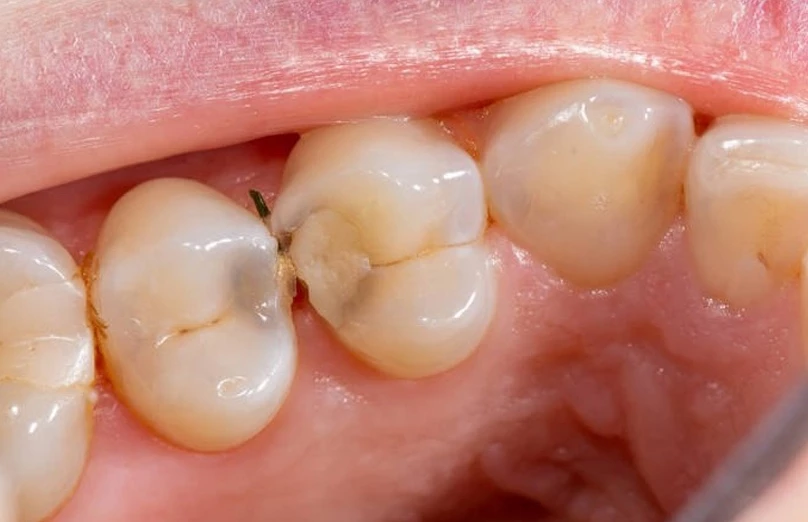

La caries interproximal se forma en los puntos de contacto entre dientes adyacentes. Al no ser visible a simple vista, suele detectarse tarde, cuando la lesión ya alcanzó la dentina. Un diagnóstico oportuno evita tratamientos más complejos como endodoncias o coronas.

La placa bacteriana se acumula fácilmente entre dientes, especialmente si no se usa limpieza interdental. Los ácidos producidos por bacterias ante la ingesta frecuente de azúcares desmineralizan el esmalte, avanzan a dentina y generan cavitación.

Las lesiones iniciales no duelen. Cuando hay sensibilidad al frío, dulce o al morder, la caries probablemente ya alcanzó dentina. Alimentos que se impactan entre dientes o cambios de color también son señales de alerta.